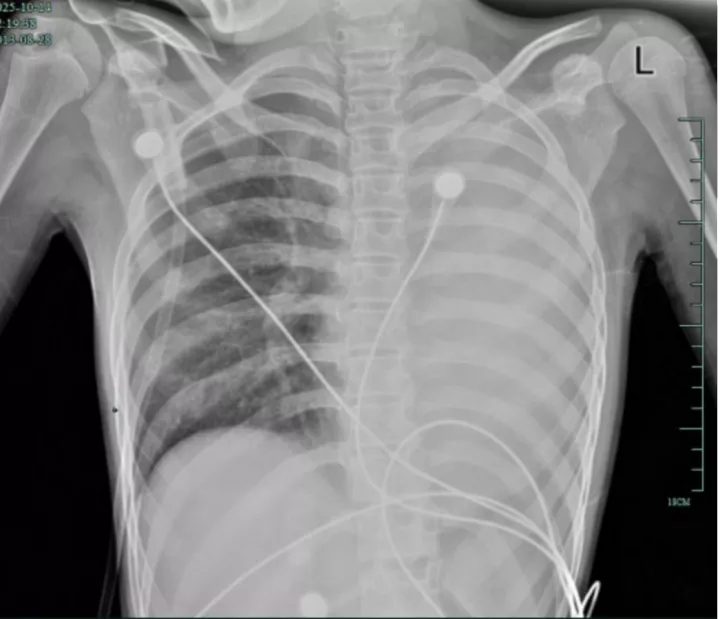

治疗前,左肺呈“白肺”状态

治疗后,“白肺”被吸收,心脏边缘清晰可见

入院后,她很快出现呼吸急促、胸闷胸痛,只能靠5L/min的面罩吸氧维持血氧,胸片显示左肺已完全呈 “白肺”

改变,肺部炎症进展迅猛。

值得高兴的是,笑笑的“白肺”基本吸收,恢复如常,没有留下严重的并发症。